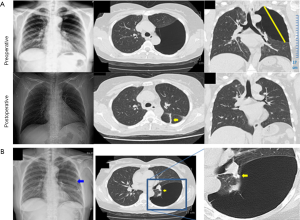

A chest X-ray showed large lucent area over the left thorax (Figure 1A), in the air space the lack of vessels coursing, the location of the upper lobes absence of visible other smaller bullae and concave surface of lung was not present on image findings were suggestive of a pneumothorax. And then, a venous catheter as left chest tube was inserted under the diagnosis of spontaneous pneumothorax but follow-up chest radiography showed no expansion of the left lung (Figure 1B). Computed tomography of chest subsequently demonstrated that a giant bulla occupying the left thorax with left upper and lower lobes compressive atelectasis and a nodular shadow was presented in the oblique fissure of left lung (Figure 1A). Laboratory studies were unremarkable.

Microscopical examination of the giant bulla showed the bulla wall is fibrous connective tissue, coating layer of flat cells, accompanied by a small amount of inflammatory cell infiltration (Figure 3A) (hematoxylin and eosin, original magnification ×4). The epithelial lining of bulla wall was positive for thyroid transcription factor 1 (TTF-1) and negative for CD1a, human melanoma black-45 (HMB-45), CD-10 or Ki-67 (Figure 3B). In addition, trabecular bone, cartilage, adipose tissue and irregular glandular cavity like structure were found in the nodular lesion, and the cell atypia was not obvious (Figure 3A). In accordance with the above findings, the final diagnosis was consistent with concomitant GBE and a pulmonary hamartoma arose from the bulla wall. After surgical resection via VATS, the lung was re-expanded well and no air leak was noted (Figure 1A), chest tube was removed on second postoperative day. The patient was completely recovered without any event and was discharged. She is currently asymptomatic and doing well after 9 months of follow-up.

As an old topic, the giant bullae of the lung and pneumothorax were usually mimicking each other (10-14), the diagnosis may sometimes pose a challenge. Since the differentiation between tension pneumothorax (TPX) and a giant bulla may be very difficult (10), in present case, chest radiography findings also easy to be misdiagnosed as TPX and a venous catheter as chest tube was inserted left thorax, fortunately without rupturing the bulla (Figure 1B). But in fact, the therapies of these two similar lesions are completely different. So that, we must be comprehensive analysis of medical history, sex, smoking and family history, physical examination and radiology for true diagnosis.